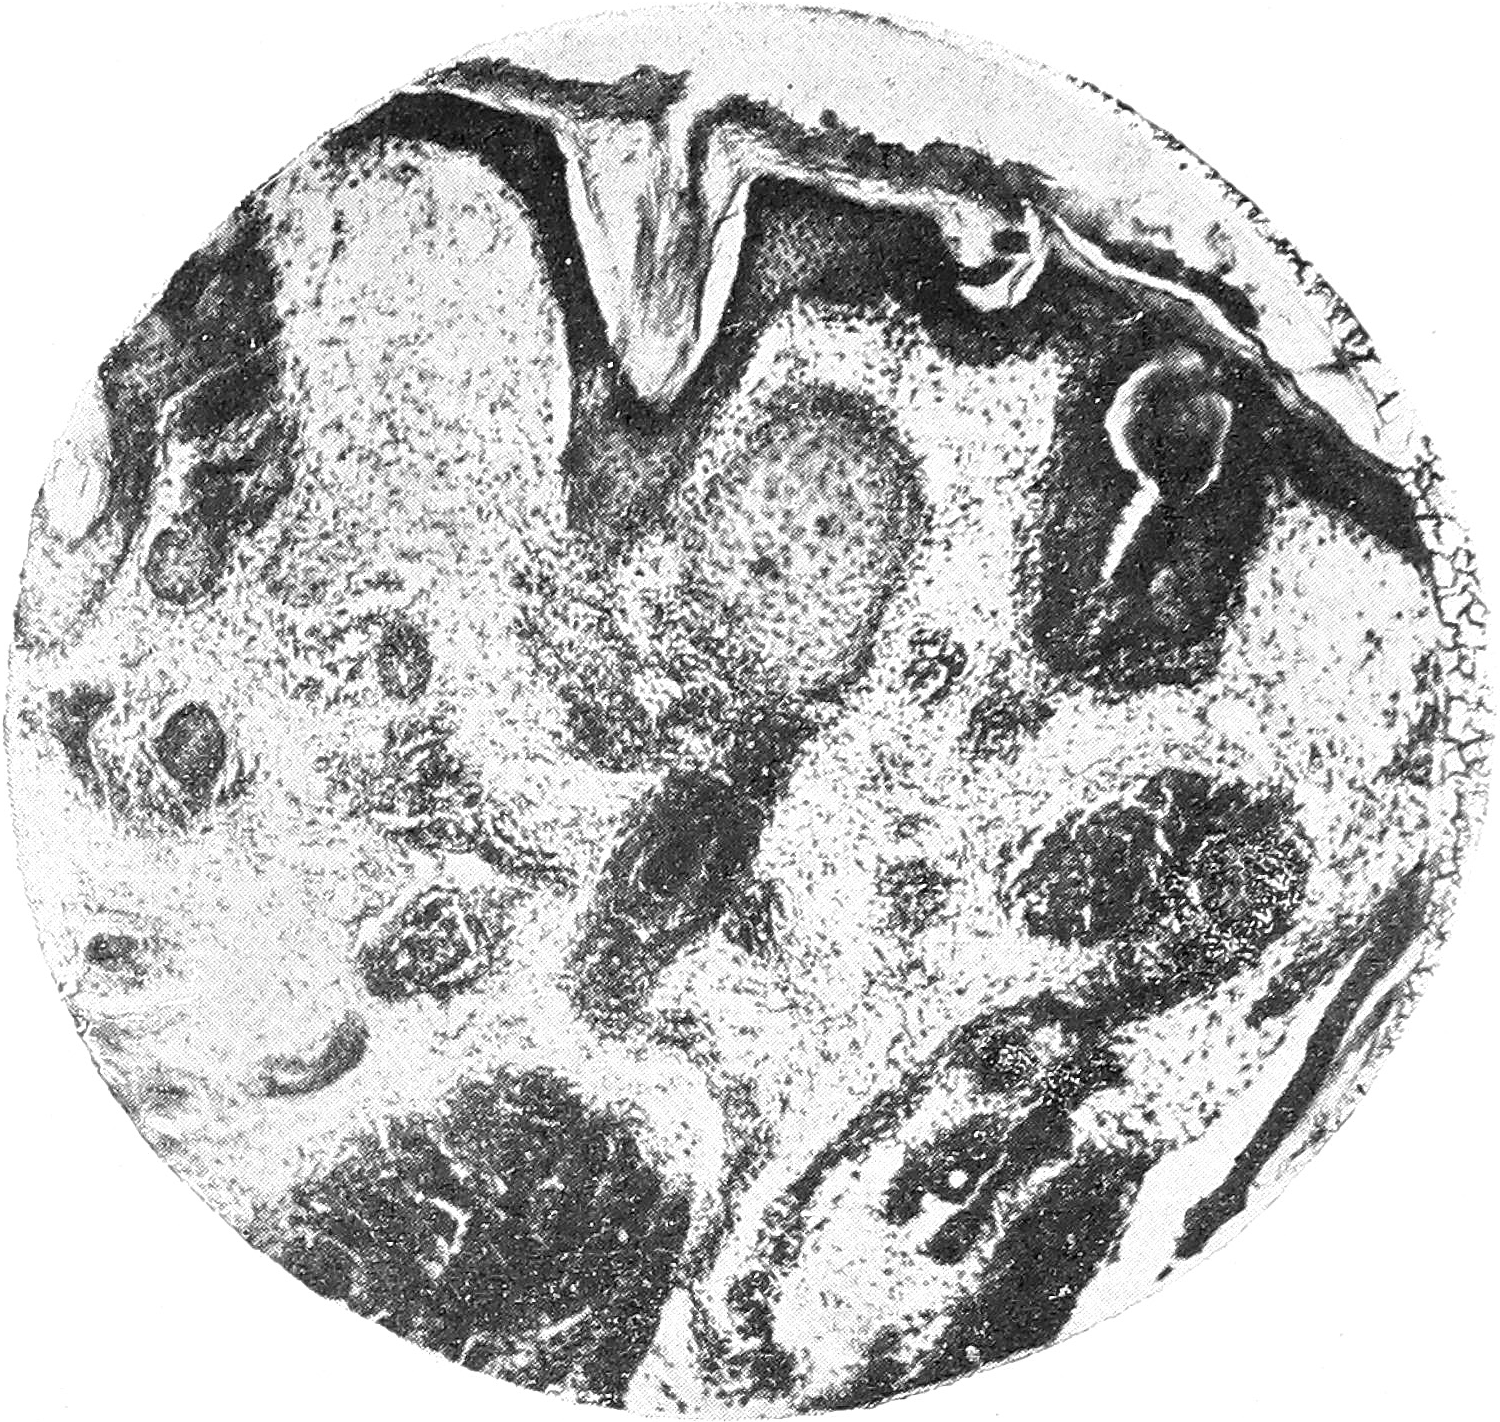

Биописия № 1 (с волосистой части головы) (рис. 1). Роговой слой почти нормальной толщины, местами разволокнен или слущен, изредка местами имеется незначительно выраженный паракератоз. Расширенные устья сально-волосяных фолликулов заполнены роговыми массами. Зернистый слой большею частью выражен хорошо, лишь в очагах парактератоза выражен неясно. В rete Malpygii мутное набухание эпителиальных клеток, незначительная вакуолизация и интерстициальное воспаление. Граница между эпидермисом и дермой невезде отчетливо выражена. По всей дерме, в сосочковом и подсосочковом слое, имеется диффузная, не очень густая инфильтрация; этот инфильтрат густо группируется вокруг сосудов, которые представляются значительно расширенными. Особенно расширены сосуды поверхностной сети дермы, в которых можно отметить и набухание эндотелия. Некоторые сосуды наполнены кровью. Местами имеются значительные кровоизлияния в дерму, иногда захватывающие значительную часть препарата. Наибольшие изменения мы находим в сально-волосяных фолликулах и потовых железах. В глубоких частях дермы и даже отчасти в подкожной жировой клетчатке встречаются также очаги инфильтрата, причем очаги эти почти всегда локализуются около тех или иных придатков кожи, преимущественно вокруг сально-волосяных мешечков у устьев их, у потовых желез, и mm. erectores pilorum. Процесс не ограничивается, однако, лишь тем, что инфильтрат окружает все придатки кожи,—-инфильтрат этот проникает и в самые волосяные мешечки и сальные железы (рис. 2). Там, где имеется диффузный и достаточно мощный инфильтрат, там коллагенная и эластическая ткани отсутствуют; эластическая ткань сохранена только в промежутках между очагами инфильтрата. Пронизанные инфильтратом придатки кожи находятся в стадии расплавления. Инфильтрат состоит, главным образом, из лимфоцитов, однако встречаются и др. элементы, как, например, плазматические клетки, фибробласты и тучные клетки.

Рис. 2.